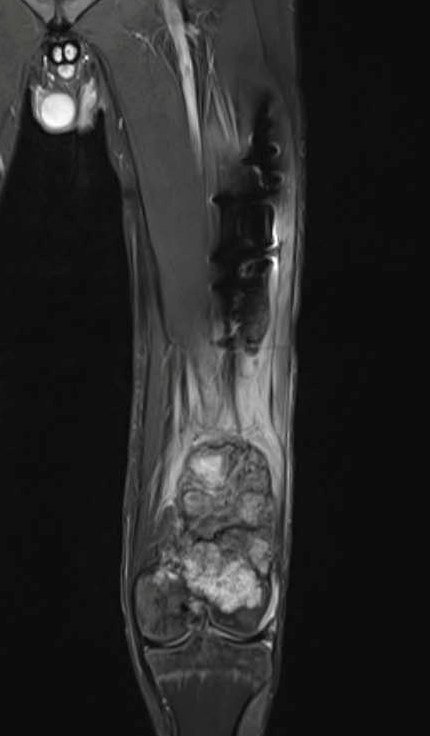

Фото: МРТ остеогенная саркома нижней трети левой бедренной кости

Выполнение лишь одного метода визуализации не позволяет достаточно оценить данную патологию, например, рентгенография и компьютерная томография позволяют детально оценить изменение костной ткани, однако из-за специфики оптических свойств не дают полного представления о мягкотканных структурах и распространении по костномозговому каналу, что требует выполнения магнитно-резонансной томографии. Оценить распространение заболевания в целом позволяет применение различных методов радионуклидной диагностики – остеосцинтиграфии, ОФЭКТ и ПЭТ компьютерной томографии.

Диагностика данной патологии состоит из нескольких этапов. Первым является сбор анамнеза и истории заболевания при клиническом осмотре онколога. Затем выполнение различных лучевых методов визуализации: рентгенографии, ультразвукового исследования, компьютерной и магнитно-резонансной томографии, сцинтиграфии, а иногда и протонно-эмиссионной томографии.